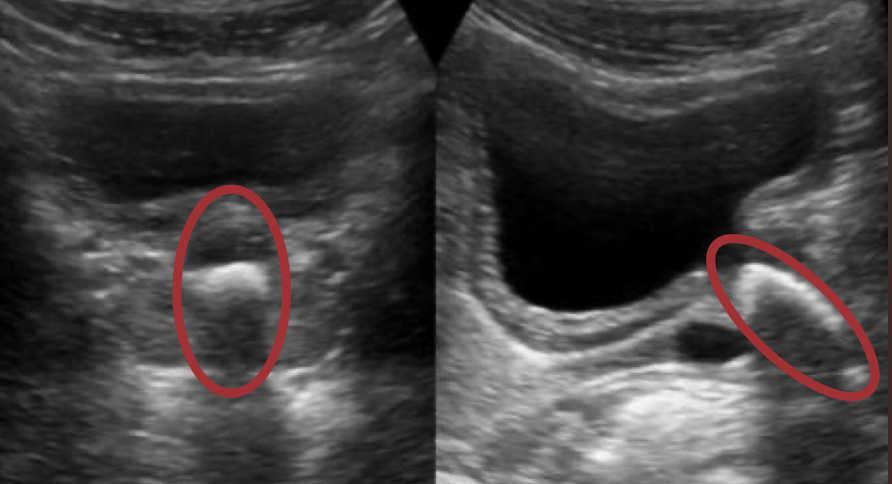

prominent columns of Bertin

invagination of cortex into medulla; indent of renal sinus (between pyramids)

??